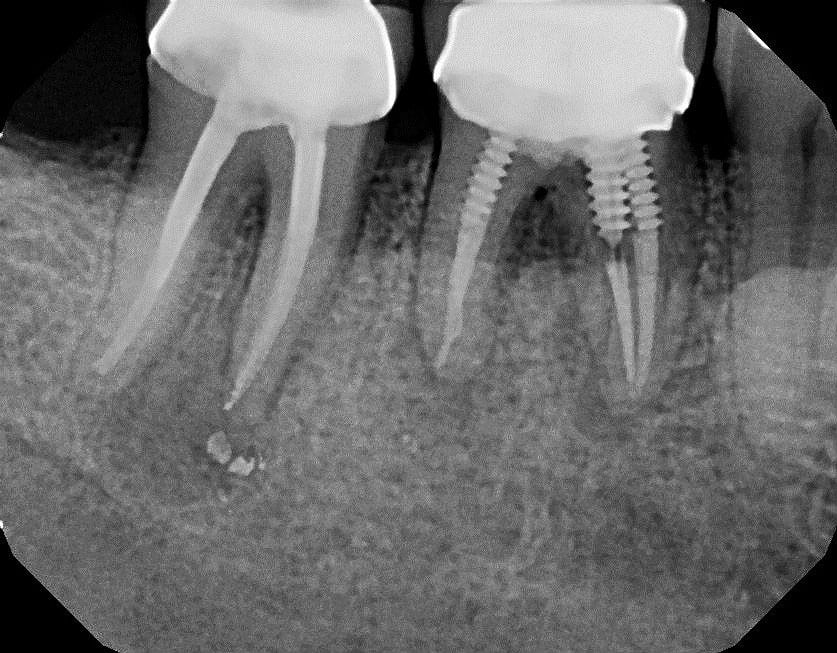

From www.shutterstock.com

3d Render Dental Bone Grafting Membrane Stock Illustration 2077218118 Bone Graft Membrane Smell Soggy yellow stuff under the stitches (was gray the first couple days), but had a. Other times, it's to support a tooth that's lost some supporting bone due to gum disease. Your success is based on numerous factors including how well your bone grafting was performed. Can you tell me why i have that nasty taste and smell? What are. Bone Graft Membrane Smell.